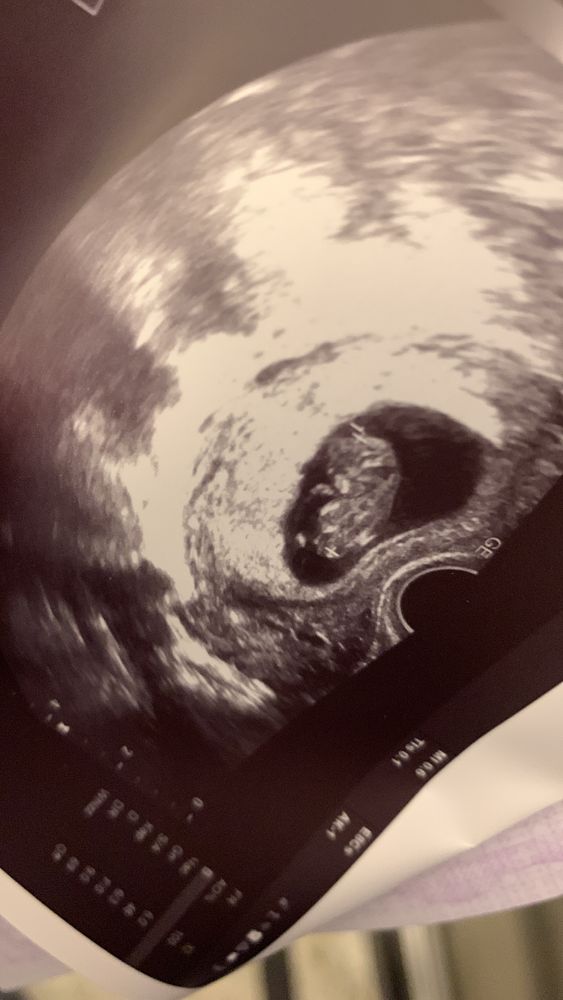

10 недель и 12 недель ☺️ сейчас он уже в экран не помещается 🥹